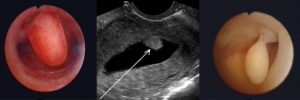

- Стандартный осмотр на кресле. Позволяет выявить аномалии строения внутренних органов, наличие воспалений и дефектов слизистой оболочки влагалища.

- Ультразвуковое исследование (УЗИ), обычно с помощью трансвагинального датчика. Этот метод показывает толщину слизистой оболочки, ее соответствие фазе цикла, а также наличие структурных патологий в органах малого таза.

- Доплерометрия сосудов матки. Обычно проводится в комплексе с УЗИ. Исследование определяет качество кровоснабжения органа.

- Диагностическая гистероскопия – по показаниям. Осмотр полости матки с помощью микрокамеры показывает наличие небольших миоматозных узлов, полипов и других новообразований. В ходе этой же процедуры они могут быть удалены.

Для определения достоверных причин гипоплазии используют методы биопсии и гистероскопию. Обязательным будет проведение гистологии. При исследованиях структурных свойств эндометриального железистого слоя выясняют, почему произошли нарушения, из-за чего рецепторов стало меньше и насколько изменились клетки.

Не только толщина влияет на успешность имплантации. Есть еще такой показатель эндометрия, как трехслойность. Даже при тонком слое беременность вполне возможна, если на ультразвуковом исследовании визуализируются все три главных слоя для надежного прикрепления эмбриона.

Определить кровоток в матке можно только при ультразвуковом исследовании с допплерометрией.